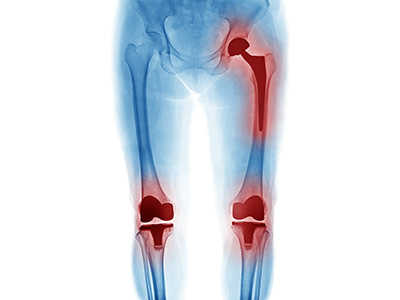

Failed Hip and Knee Replacements

Conventional, primary total hip replacement is a durable operation in majority of patients. A hip replacement is a mechanical device with parts, most commonly referred to as a “ ball and socket,” that are assembled before and during the operation.